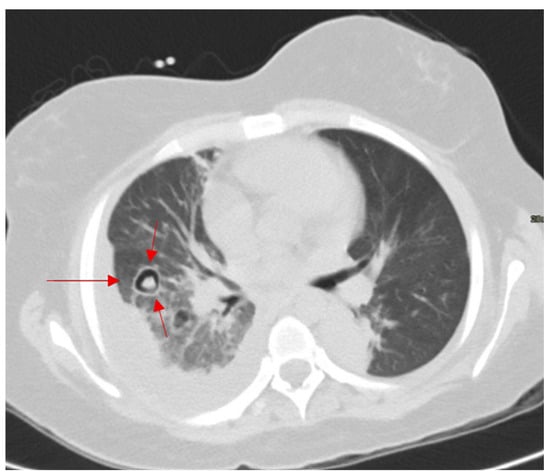

2.15.2. On CT

- Pinto, P. The CT Halo Sign. Radiology 2004, 230, 109–110. [Google Scholar] [CrossRef] [PubMed]

- Georgiadou, S.P.; Sipsas, N.V.; Marom, E.M.; Kontoyiannis, D.P. The diagnostic value of halo and reversed halo signs for invasive mold infections in compromised hosts. Clin. Infect. Dis. 2011, 52, 1144–1155. [Google Scholar] [CrossRef] [PubMed]

- Marchiori, E.; Penha, D.; Nobre, L.F.; Hochhegger, B.; Zanetti, G. Differences and similarities between the double halo sign, the chest CT target sign and the reversed halo sign in patients with COVID-19 pneumonia. Korean J. Radiol. 2021, 22, 672. [Google Scholar] [CrossRef] [PubMed]

| Halo Sign (CT chest) | CT (thorax) | Early invasive pulmonary aspergillosis, hemorrhagic metastases, vasculitis, COVID-19 pneumonia | Sensitive but not specific; overlaps with infection and inflammation | Recognized early markers in immunocompromised patients; prompts antifungal therapy but requires correlation with clinical/lab data. |